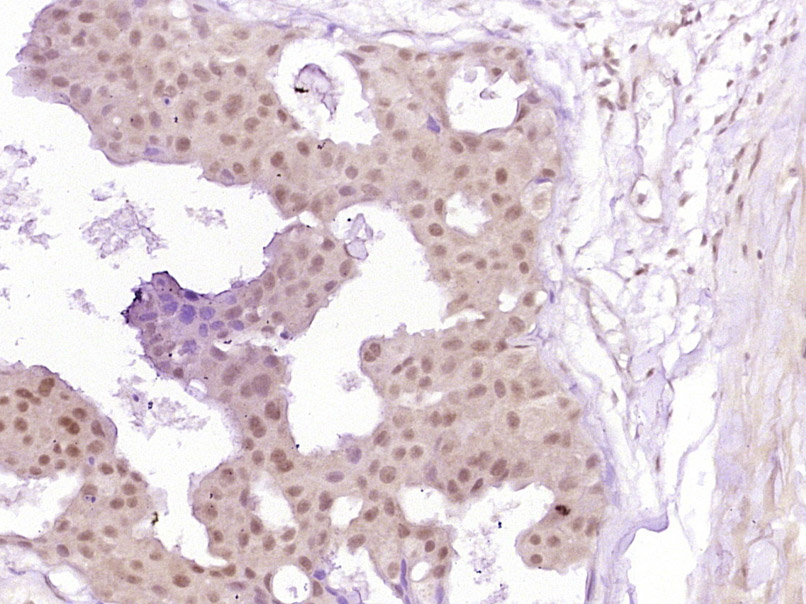

Paraformaldehyde-fixed, paraffin embedded (Human breast carcinoma); Antigen retrieval by boiling in sodium citrate buffer (pH6.0) for 15min; Block endogenous peroxidase by 3% hydrogen peroxide for 20 minutes; Blocking buffer (normal goat serum) at 37°C for 30min; Antibody incubation with (phospho-Smad3 (Ser213)) Polyclonal Antibody, Unconjugated (bs-5459R) at 1:400 overnight at 4°C, followed by operating according to SP Kit(Rabbit) (sp-0023) instructionsand DAB staining.